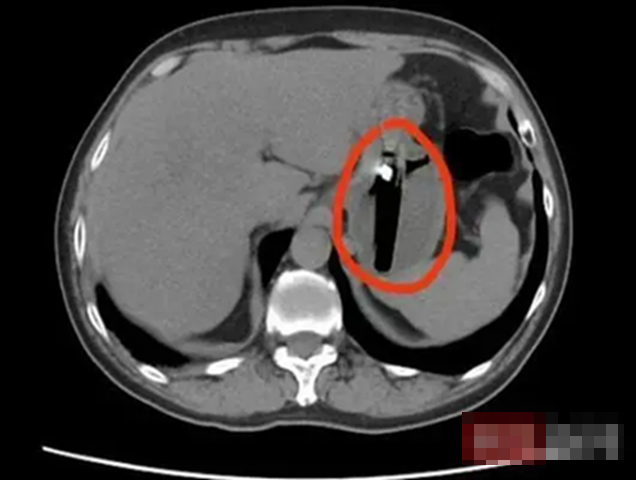

Kết quả chụp CT khiến cả bệnh nhân lẫn bác sĩ bất ngờ: trong dạ dày của anh có một dị vật dài khoảng 8cm. Sau khi khai thác kỹ tiền sử, bác sĩ nghi ngờ dị vật này chính là một chiếc bật lửa mà bệnh nhân đã vô tình nuốt phải trong một lần say rượu cách đó khoảng một tháng.

Người đàn ông 36 tuổi đau bụng dữ dội, đi khám phát hiện thứ "lạ đời" không ai nghĩ được nó nằm bên trong- Ảnh 1.